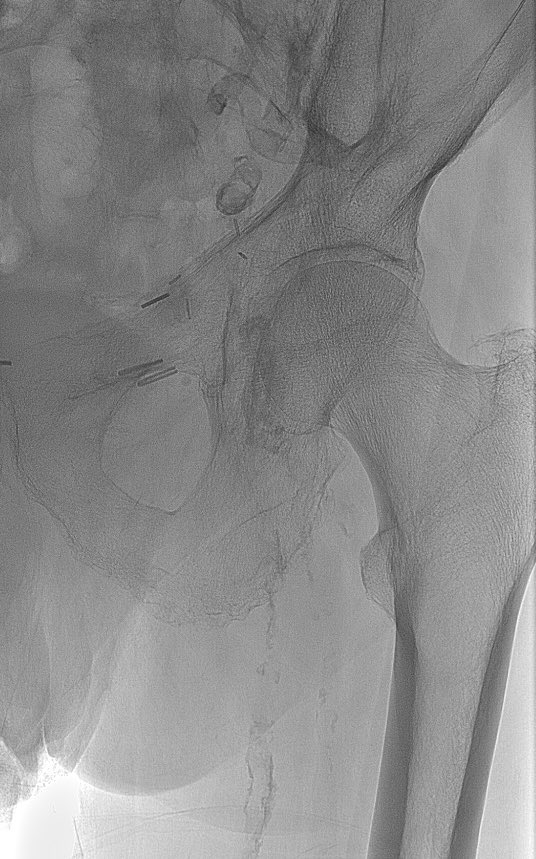

60M presents for evaluation. Runs 2 miles daily w/no symptoms and BP, lipids, A1c optimally controlled. Another doc orders a stress test given family history of CAD. 13:00 Bruce, 100% max pred HR, no symptoms, 6% rev inferior defect read as ischemia. What do you do?